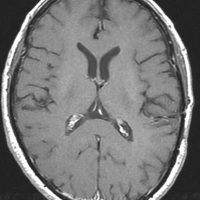

- MRIで転移性脳腫瘍は,低信号から高信号を示すものまでいろいろです

- ガドリニウム造影剤で増強されてくっきり写ります

- 腫瘍中心壊死のためリング状に増強されると膠芽腫との鑑別が難しいことがあります

- 周辺脳浮腫(腫瘍の周囲の脳が腫れている)が特徴です

典型的な転移性脳腫瘍(単発)のMRI

腺癌の左前頭葉転移です。左のガドリニウム造影剤を使った画像では腫瘍が白く写っています。腫瘍の内部が一部壊死しているので黒っぽく見えます。右はフレア画像です。腫瘍の周囲の脳が腫れて脳浮腫(白く滲むようなところ)を生じています。